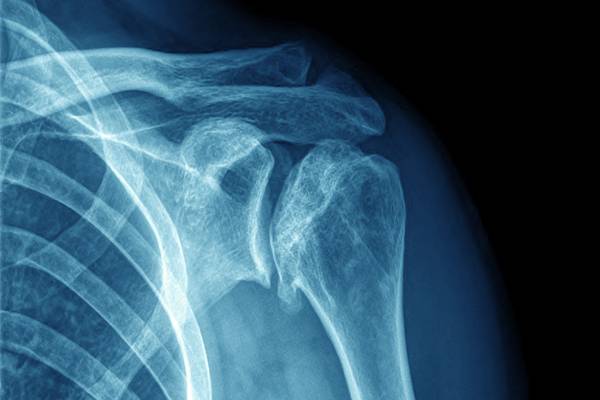

MRI and CT scanners are crucial pieces of equipment that are used in diagnosing a wide range of conditions from cancer to bone damage. Dr Julian Elford, Consultant Radiologist, said:

“CT and MRI machines start to become technically obsolete at 10 years. Older kit breaks down frequently, is slower, and produces poorer quality images, so upgrading is critical.”